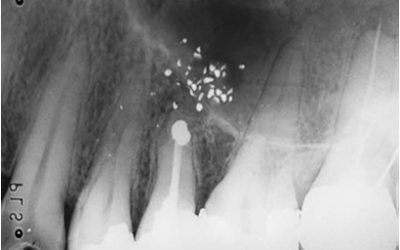

القلع و إعادة الزرع أو إعادة الزرع المقصودExtraction And Replantation-Intentional replantation تصنيف عام